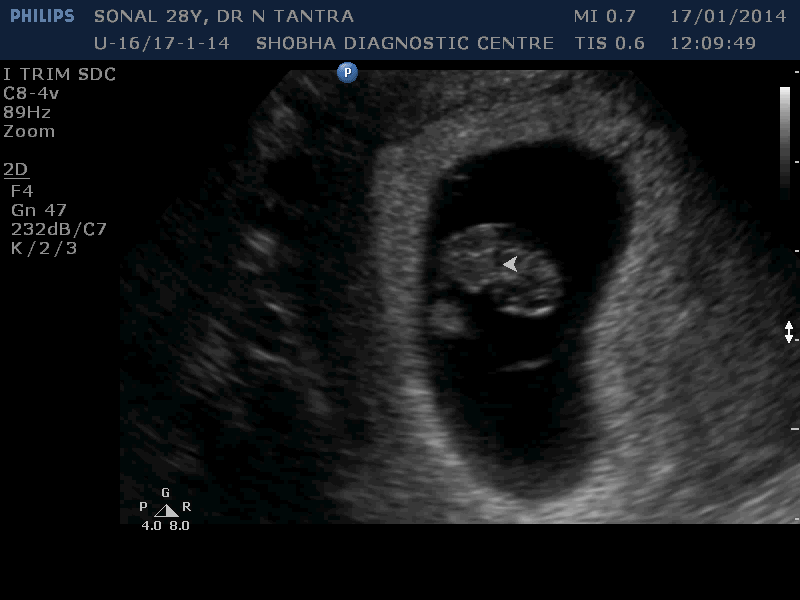

Early Sonography

Before 10 weeks

For this, Sonography is done vaginally (internal examination).